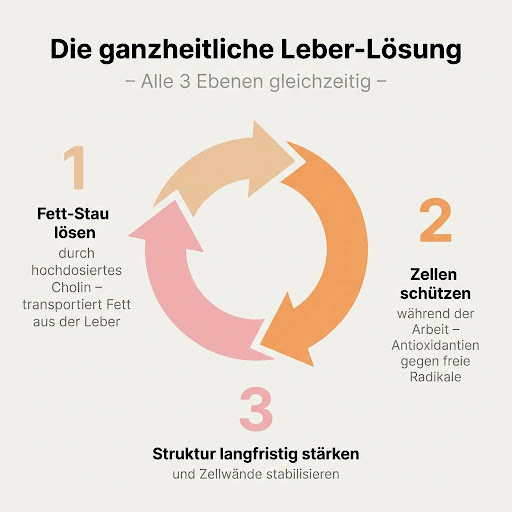

Deswegen wurde mir der Viktilabs Leber Komplex empfohlen. Der arbeitet nämlich auf 3 Ebenen und wenn man den Mechanismus einmal versteht, ergibt das einfach Sinn:

Ebene 1 löst das Kernproblem – Cholin zusammen mit Inositol und Alpha-Liponsäure sorgt dafür, dass die Leber die Fette endlich wieder verpacken und abtransportieren kann.

Ebene 2 schützt die Leberzellen während dieser Arbeit – mit hochdosierter Mariendistel, Artischocke und Bitterstoffen wie Löwenzahn und Wermut, die gleichzeitig die Gallenproduktion und Verdauung ankurbeln.

Und Ebene 3 stärkt die Zellstruktur der Leber langfristig mit Silizium aus Bambus, damit das Ganze auch stabil bleibt. Andere Produkte haben vielleicht eine oder zwei dieser Ebenen – aber keines, das ich kenne, deckt alle drei gleichzeitig in sinnvollen Dosierungen ab.